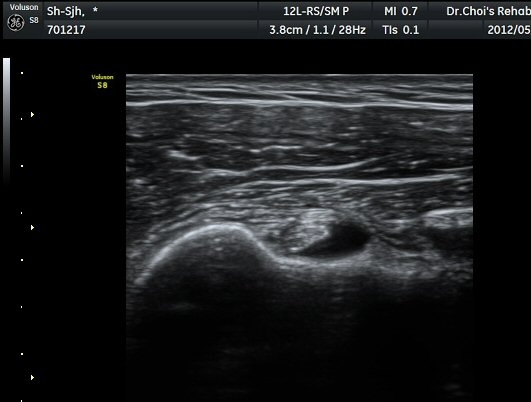

Á߸³»óÅ ¾î±ú ¾Õ Ⱦ´Ü¸é°Ë»ç¿¡¼­ À̺ειڱ٠ÁÖÀ§¿¡ ¼ö¾×Àú·ù°¡ °üÂûµÇ°í(»çÁø 1) ÆÄ¿öµµÇ÷¯

°Ë»ç¿¡¼­ Ç÷·ùÁõ°¡°¡ °üÂûµÈ´Ù(»çÁø 2). À̵ιڱ٠Á¾´Ü¸é°Ë»ç¿¡¼­µµ °Ç ÁÖÀ§ ¼ö¾×Àú·ù°¡ È®ÀÎ